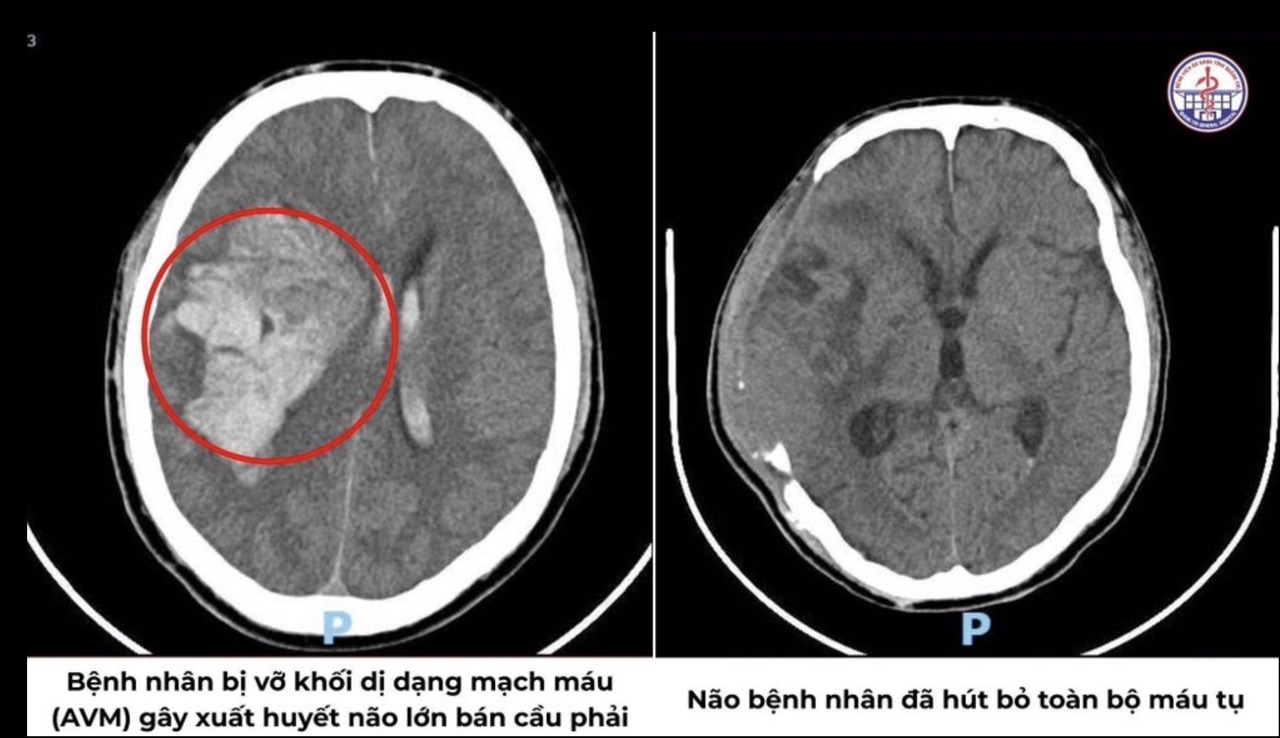

Kết quả chẩn đoán cho thấy bệnh nhân bị xuất huyết não nặng, nhiều khả năng do vỡ dị dạng thông động – tĩnh mạch (AVM). Hình ảnh ghi nhận khối AVM nội sọ kích thước lớn (37 x 58 x 87 mm), kèm khối máu tụ lan tỏa, gây chèn ép và đẩy lệch đường giữa não. Trước tình thế nguy cấp, quy trình “báo động đỏ” được kích hoạt.

Các bác sĩ quyết định mổ mở sọ khẩn cấp để cầm máu, lấy máu tụ và giải áp. Sau 3 giờ phẫu thuật căng thẳng, ekip Ngoại Thần kinh đã kiểm soát được điểm chảy máu, giải phóng chèn ép, giúp bệnh nhân thoát khỏi nguy kịch.

Ở giai đoạn tiếp theo, khi tình trạng ổn định hơn, bệnh nhân tiếp tục được chẩn đoán có AVM tại vùng thái dương – đỉnh phải (47 x 30 mm), cấp máu bởi nhiều nhánh động mạch não giữa. Các bác sĩ tiến hành can thiệp mạch DSA, luồn catheter qua động mạch cảnh trong, bơm keo tắc mạch chọn lọc từng nhánh nuôi. Tỷ lệ nút mạch đạt trên 95%, giảm tối đa nguy cơ tái xuất huyết.